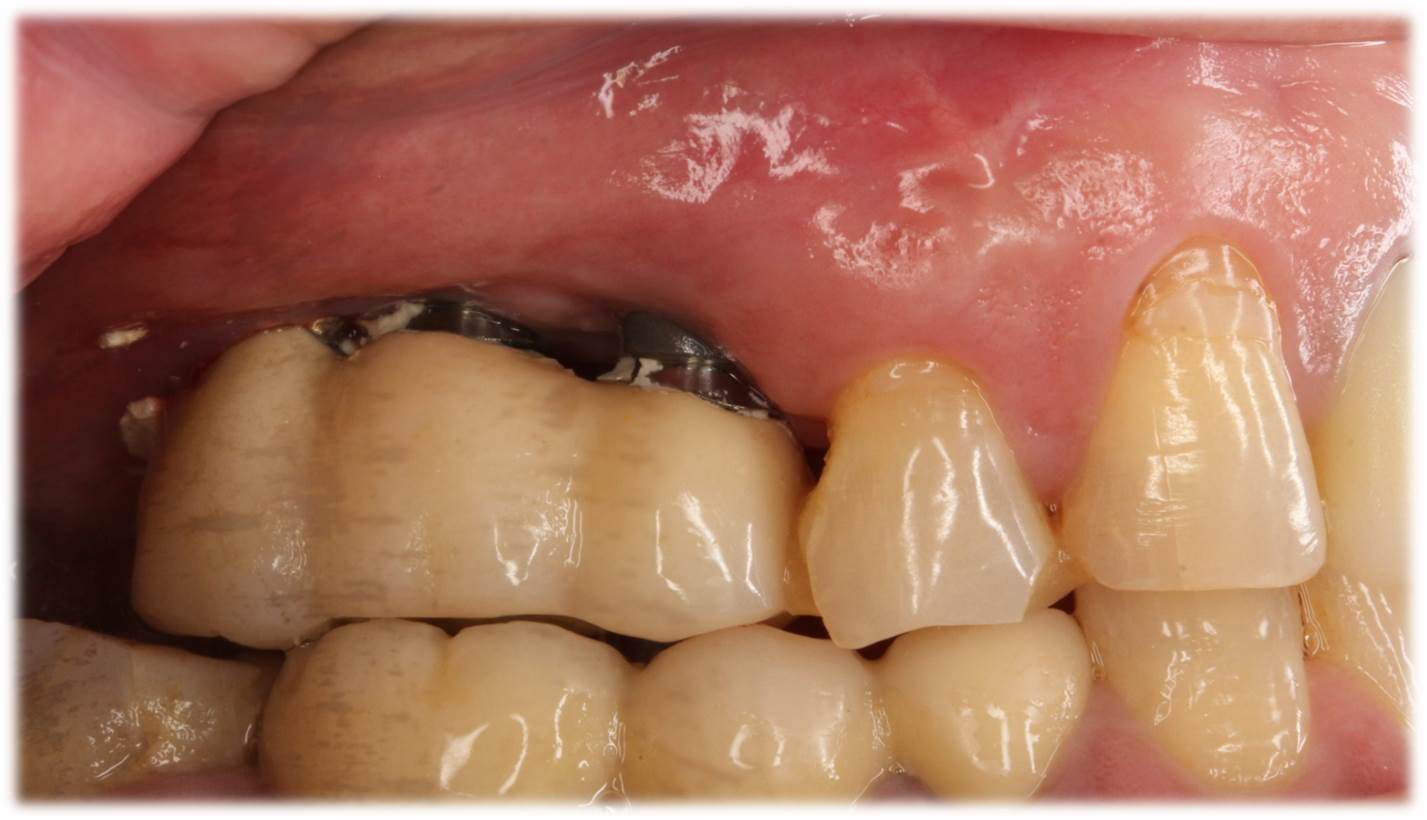

「他院通院中ですが、セカンドオピニオンを受けたい」というご要望が増えてきています。画像の症例は、奥歯のインプラントの上部構造(被せ物)に関するセカンドオピニオンでした。「最近、口の中に入れたけれども食べ物が入って詰まってしまう」との訴えがありました。

インプラント体のスレッド部分(ネジ)が見えてしまっており、被せ物と歯茎の間にも大きな間隙があるのが問題です。通常は歯茎の下方からの立ち上がりを作るように、予め計画するのですが、スレッド部が見えている現状では、上部構造の被せ直しをする以外に、改善は不可能と思われました。また、仮留めのセメント材料が多量に残っている状態でしたので、このままではインプラント周囲炎を惹起する可能性もあることを説明し、通院中の歯科医院にも文書での状況報告をさせて頂きました。